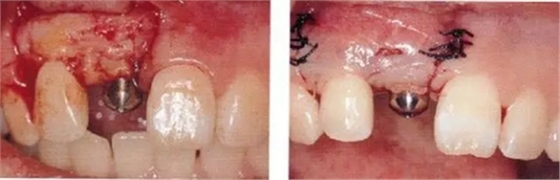

▲圖44-4,5

圖44-6

圖44-4~6 拔牙后通過骨移植材以及結(jié)締組織移植(CTG)進行GBR。